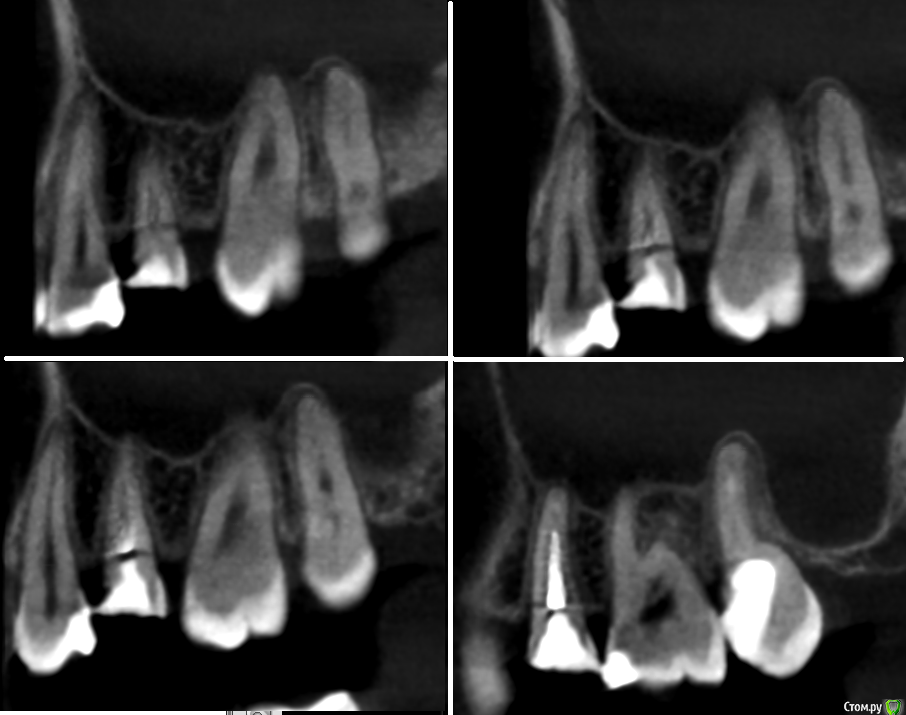

kurkuma Опубликовано 27 июня, 2017 Поделиться Опубликовано 27 июня, 2017 Всем добрый день! Ситуация такая: лечили мне зуб 15, после последней промывки каналов и закладки лекарства за верхушку корня зуба (йод+метронидазол+не помню что) вечером этого же дня из носа полило и заложило пазуху. По кт выявили гайморит. Теперь у меня встал вопрос- продолжать ли спасать зуб(вкладка+коронка), которую предлагают в клинике или зуб лучше удалить( как советует лор). Я например по кт вижу одни поперечные трещины, что подразумевает удаление зуба. В клинике сказали всё нормально, трещин нет(????) лечите гайморит. Что подскажете вы, уважаемые участники форума? Ссылка на комментарий

St. Опубликовано 27 июня, 2017 Поделиться Опубликовано 27 июня, 2017 Корни этого зуба действительно выходят в гайморову пазуху, это вариант нормы.То что смушает вас на снимке скорее всего артефакт. Исходя только из снимка показаний удалению не вижу. 3 Ссылка на комментарий